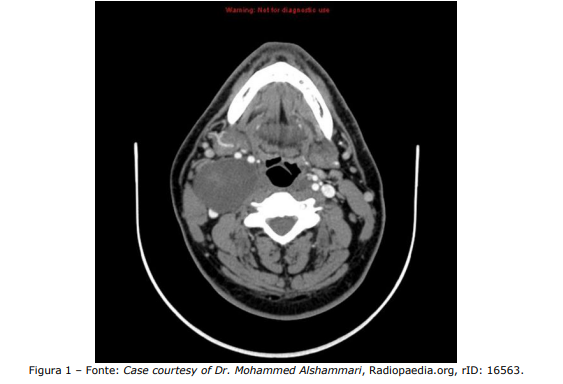

Homem, 45 anos, vem à consulta no ambulatório de cirurgia de cabeça e pescoço por queixa de abaulamento cervical em topografia jugulocarotídea alta à direita, assintomático. Refere massa há cerca de 4 anos, com crescimento progressivo, porém lento. Nega episódios inflamatórios prévios. Ao exame, a massa é fibroelástica, indolor, móvel no sentido anteroposterior, porém não no craniocaudal. Nesse sentido, analise a Figura 1 a seguir, em que a TC é mostrada:

Enunciado 4483719-1

Em relação ao caso, assinale a alternativa que indica a hipótese diagnóstica mais provável.